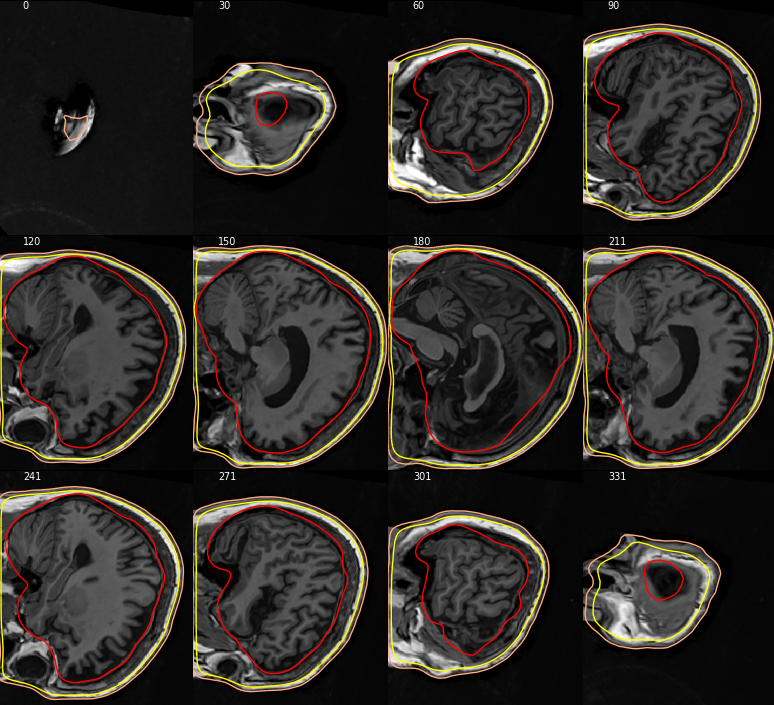

@larsoner Sorry for the late feedback. I do not have the MRI that prompted me to submit the issue #7221 anymore because I went around the issue by preprocessing all my MRI to a "conform" space in the meantime. But I always end up having to move data between pipelines and almost always run into issues with incompatible coordinate systems. So I found some MRI from a different project (originally processed in CIVET rather than FreeSurfer) that were not preprocessed to a conform to space and that is what I got: So... the fix works to the extent that it puts the MRI in coronal view when it is supposed to put it in this view. I think the rest is more about what level of user-friendliness you want to support (i.e., whether or not you would like to have it 100% aware of coordinate system so that it would invert axes if needed to display it in a standard orientation or leave it to the user to provide their MRI in a given coordinate system). At least, right now, it does the volume along the requested axis. FYI, there appears to be some bug in the management of paths: The call at "In [9]" should works as, according to the docstring, the subjects_dir argument can be left to None, in which case "the path is obtained by using the environment variable SUBJECTS_DIR." This error seems to have been introduced with this fix because it works fine when I revert to the MNE version I had before applying this fix. |